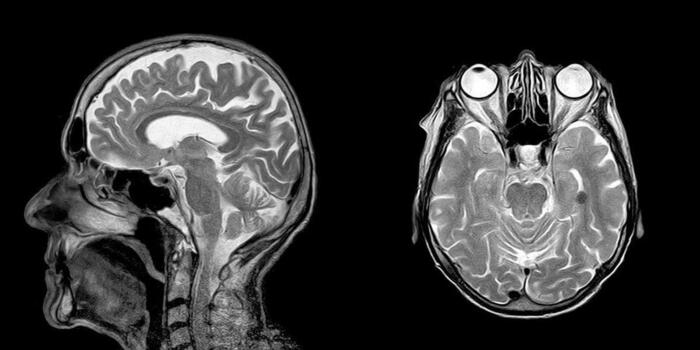

- МРТ головы и головного мозга;